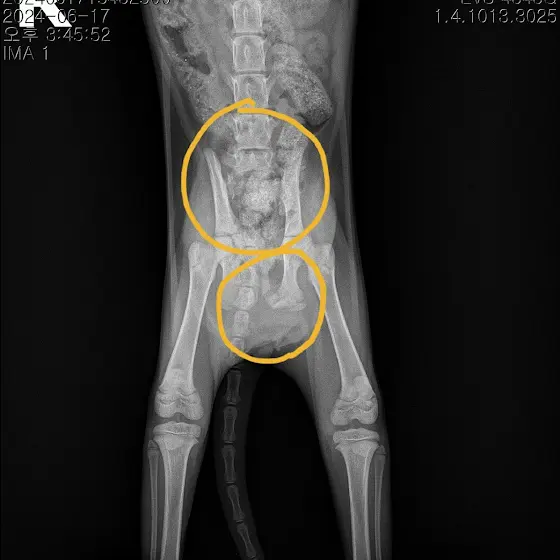

✔️ 부산 사상에서 운전해서 도로를 달리던 차안에 있던 아기고양이가 미처 못나오고있다가 달리는중 나오려하면서

골반골절과 방광 탈장이 일어난것같고,

✅️ 방광탈장수술, 골반골절 수술비 마련이 시급합니다 ✅️